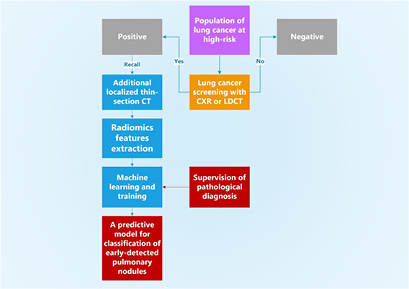

In this work, we conducted a retrospective study to investigate whether an additional procedure of localized thin-section CT is useful to further evaluate these recalled nodules and differentiate different types of early-detected nodules from lung cancer screening tests. The approach of localized thin-section CT was integrated with radiomics features extraction and machine learning. The pathological diagnosis was used to label the malignancy of nodules and supervise the machine learning. A flowchart diagram of our approach is summarized in figure 1. The quantities of classification accuracy, sensitivity, specificity, false positive rate, positive predictive value, and the area under the receiver operating characteristic (ROC) curve are used to report the performance of our technical approach of localized thin-section CT.

Figure 1. A flowchart diagram of our approach of localized thin-section CT with radiomics features extraction and machine learning. The pathological diagnosis is used to supervise the machine learning for classification. Our approach supervised by the pathological report provides a direct risk for early-detected pulmonary nodules from lung cancer screening tests.